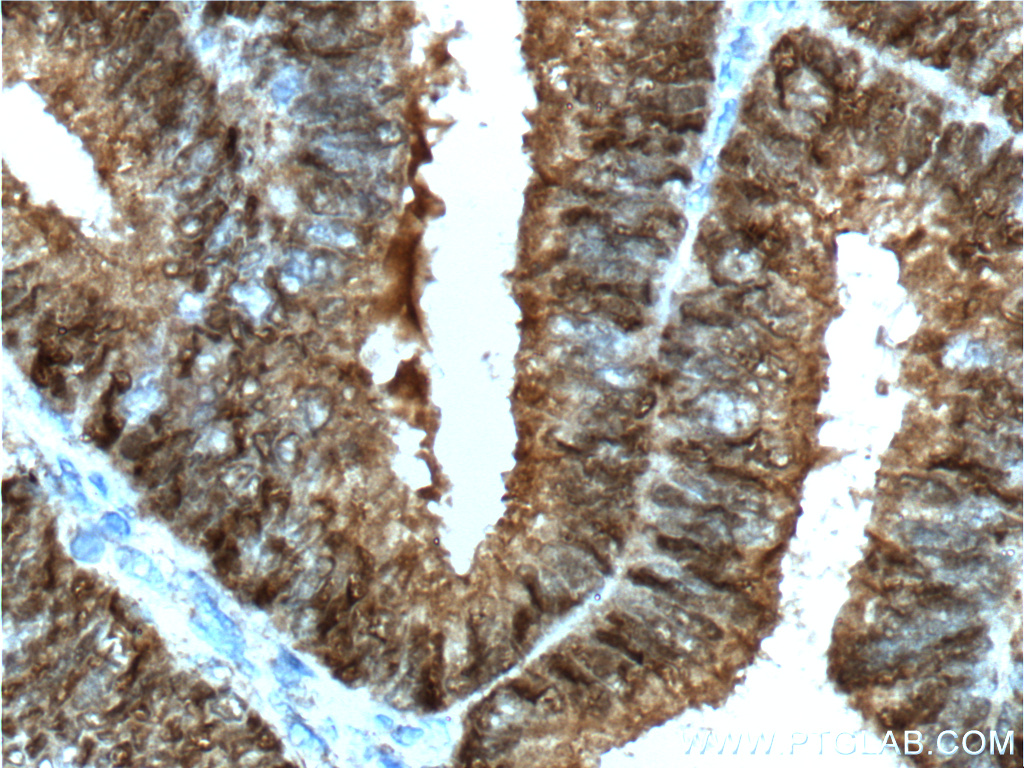

| Positive IHC detected in | human breast cancer tissue Note: suggested antigen retrieval with TE buffer pH 9.0; (*) Alternatively, antigen retrieval may be performed with citrate buffer pH 6.0 |

| Immunohistochemistry (IHC) | IHC : 1:50-1:500 |